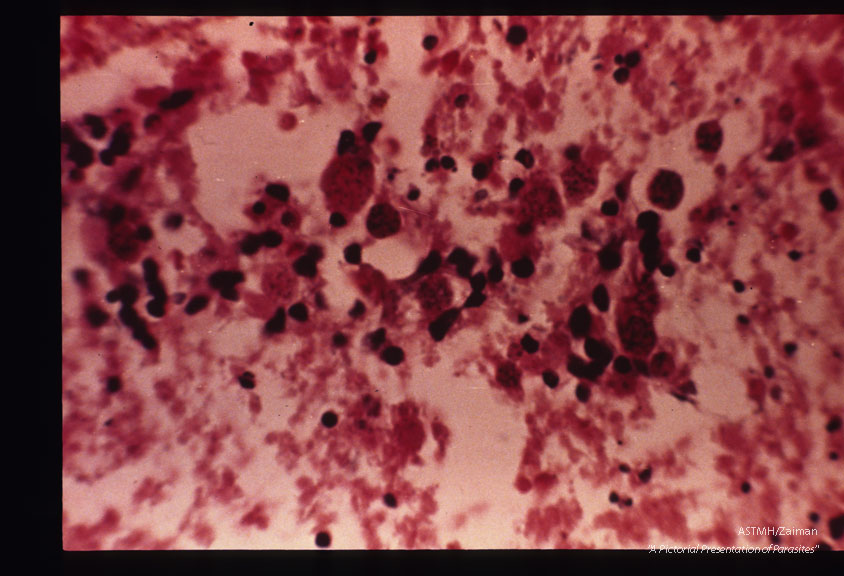

Cysts in retina of patient with positive dye test.

Toxoplasma gondii

Description: Cysts in retina of patient with positive dye test.